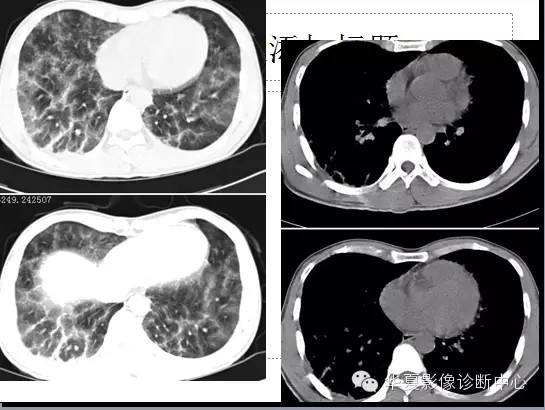

两肺野弥漫性分布的斑点及斑片状阴影,呈“暴风雪”样,病变以两中下肺野为多,部分小叶间隔增厚,心脏大小正常。纵隔窗显示右侧胸腔后下部少量积液。。

诊断:肺脂肪栓塞综合征。